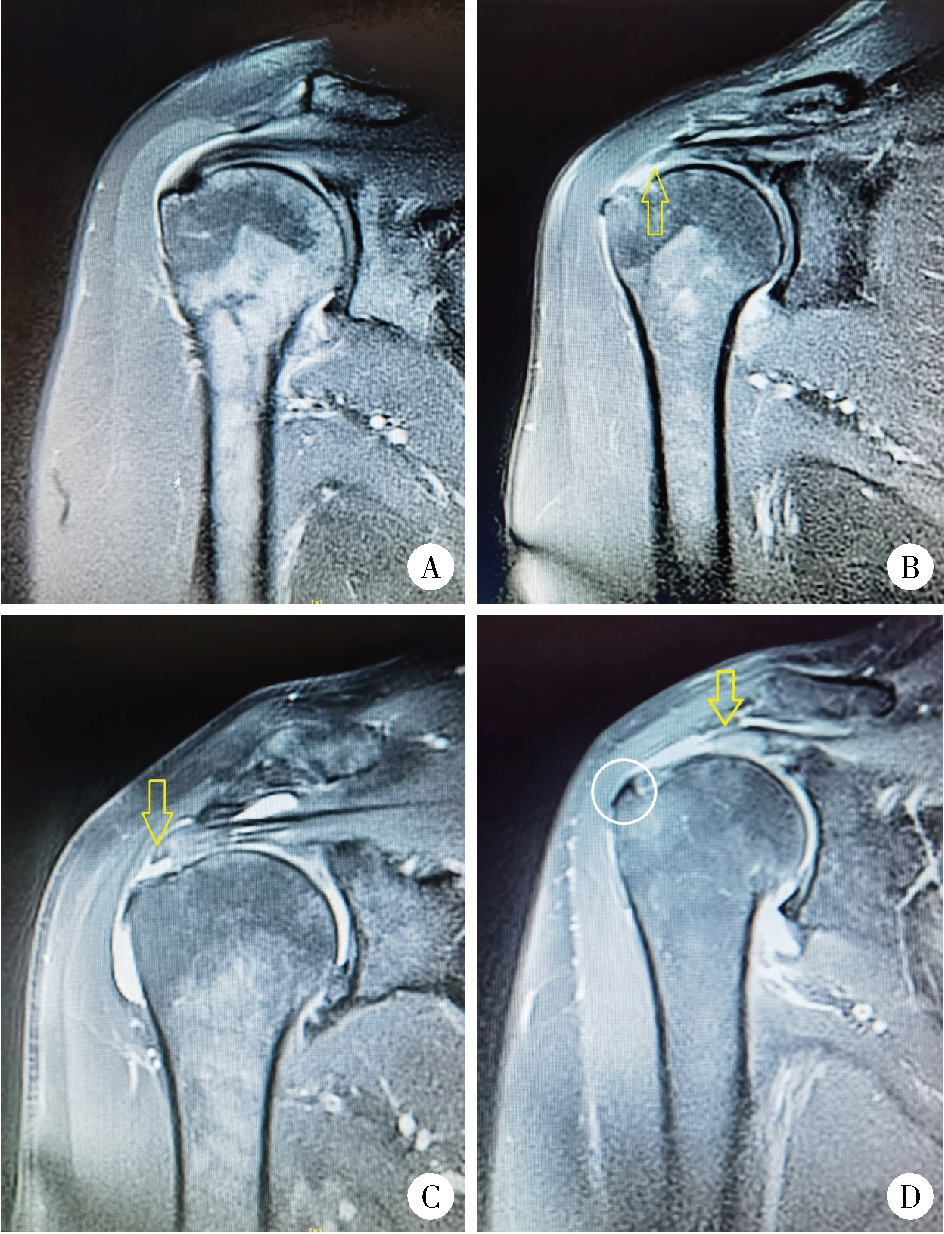

图1 各组肩袖撕裂患者的MRI影像Figure 1 MRI images of patients with rotator cuff tears in each group A, negative control group; B, partial RCTs (articular side) group; C, partial RCTs (bursal side) group; D, full-thickness RCTs group. The arrow indicates the site of RCTs, the circle marks the osteophytes of greater tuberosity of humerus. RCTs, rotator cuff tears. |